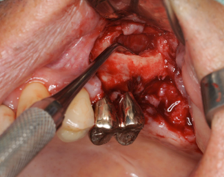

サイナスリフトとインプラント同時埋入しています。この場合だいたい9か月ほど

インプラントが骨に結合するまで待ちます

CTで人工骨がインプラントの周りに入っているのを確認しています。